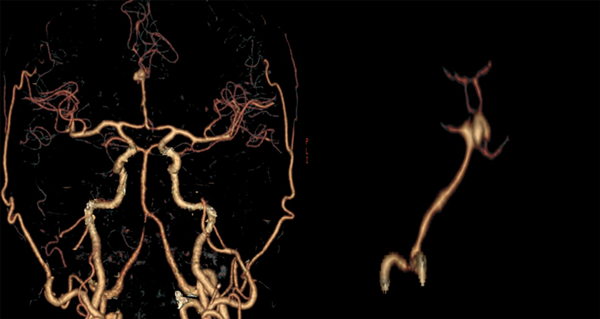

Paciente masculino de 47 años sin antecedentes patológicos de importancia, refiere inicio de enfermedad actual con cefalea súbita, severa, holocraneana, irradiada a región occipitocervical con vómitos en proyectil, desorientación, midriasis e incontinencia urinaria; es remitido a nuestra institución a los 16 días desde el inicio de los síntomas. Al ingreso se observa meningismo, trastornos en el nivel de conciencia e hipertensión arterial. En la tomografía de cerebro (TC) se observa una hemorragia subaracnoidea con un hematoma frontal bilateral. Se realiza angiotomografía cerebral donde se evidencia aneurisma sacular mediano trilobulado de ACAa (Figuras 1 y 2). Al examen físico de ingreso: bradipsíquico, bradilálico, somnoliento, desorientado, GCS 12/15 (respuesta ocular: 3, respuesta verbal: 3, respuesta motora: 6), pupilas isocóricas normorreactivas, sin focalidad de nervios craneales, vías largas: paraparesia 4/5 puntos (Daniels), rigidez de nuca leve y signo de Kernig. Se indica nimodipina 60 mg vía oral, medidas antiedema cerebral. Durante los días 2 y 24 de hospitalización se mantiene con clínica WFNS I, excepto el día 11 de hospitalización, donde se presenta deterioro neurológico por desorientación a WFNS II con evidencia de hiponatremia moderada (129 mEq/L). Se solicita tomografía cerebral simple control en la que se descarta resangrado e hidrocefalia, se indica corrección de sodio plasmático con mejoría evidente del estado neurológico a WFNS I. Se plantea intervención quirúrgica a las tres semanas del ingreso.

Figura 1. Angiotomografía cerebral. En cortes axial, coronal y sagital contrastados, se evidencia dilatación de aspecto sacular en fisura interhemisférica compatible con aneurisma de ACAa; hemorragia subaracnoidea en cisternas de la base y espacio subaracnoideo de la convexidad, hematoma intraparenquimatoso heterogéneo e irregular bifrontal.

Figura 2. Angiotomografía cerebral. En reconstrucción 3D se evidencia circuito anterior: confluencia de ambos segmentos A1 (sin presencia de complejo comunicante anterior) en un tronco arterial único A2, presenta un aneurisma sacular trilobulado mediano en su bifurcación con domos que se disponen hacia arriba y hacia adelante. Cuello: 6.16 mm, alto: 6.39 mm y ancho: 8.17 mm.